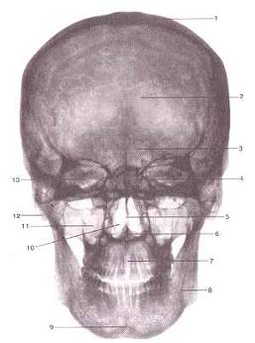

Рентгеновская картина черепа взрослого человека

Вид спереди.

1-крыша (свод) черепа;

2-лобная кость;

3-лобная пазуха;

4-ячейки решетчатой кости;

5-костная перегородка полости носа;

6-передняя носовая ость;

7-межверхнечелюстной шов;

8-нижняя челюсть;

9-подбородочный выступ;

10-полость носа;

11-верхнечелюстная пазуха;

12-сосцевидный отросток;

13-глазница.